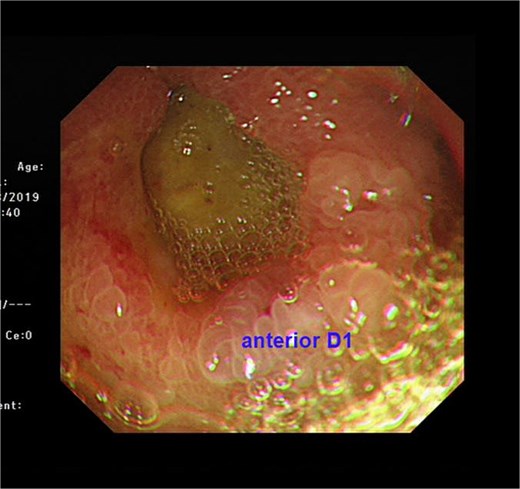

A 74-year-old man who had history of hypertension and diabetes mellitus presented with upper gastrointestinal bleeding. Upper endoscopy revealed deformed pylorus and a 1 cm deep ulcer at anterior wall of first part of duodenum (Fig. 1). Computed tomography (CT) revealed a 4.8 cm exophytic hypoenhancing mass at segment 4a of liver with dilated left intrahepatic duct (Fig. 2). There was aerobilia suggestive of choledochoduodenal fistula. There was also suspicion of diaphragm invasion. Serum carcinoembryonic antigen (CEA) was elevated to 83ug/L while alpha-fetoprotein (AFP) was normal. Both the hepatitis B surface antigen and anti-hepatitis C antibody were negative. Positron emission tomography (PET) confirmed a hypermetabolic liver tumor but no distant metastasis. The clinical diagnosis was ICC with suspected duodenal and diaphragmatic invasion. The patient was offered radical resection for tumor.